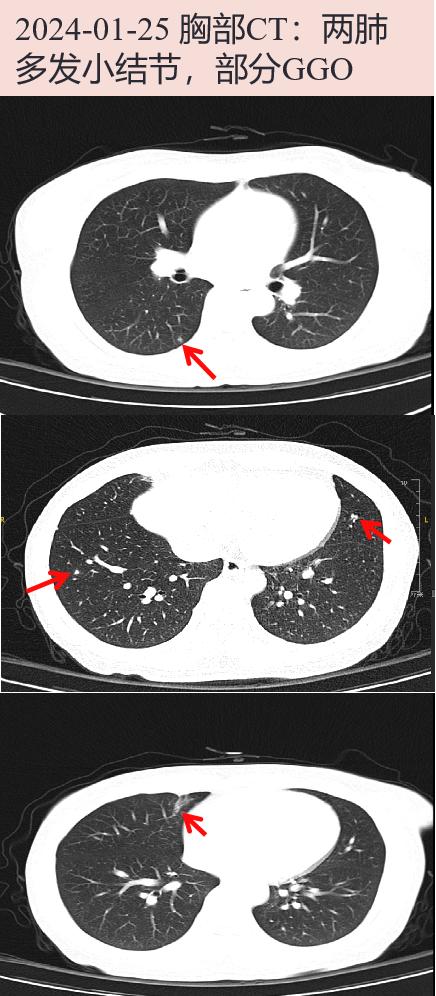

2024-01-25 心外科会诊:建议充分抗感染4周后,评估手术治疗指征。2024-01-25 胸部CT: 两肺多发小结节,部分GGO;右中肺少许慢性炎症。腹盆增强CT: 肝囊肿,右肾囊肿,脾稍大,双肾微小结石可能,膀胱可疑微小结石,子宫密度局部欠均,请结合临床随访。